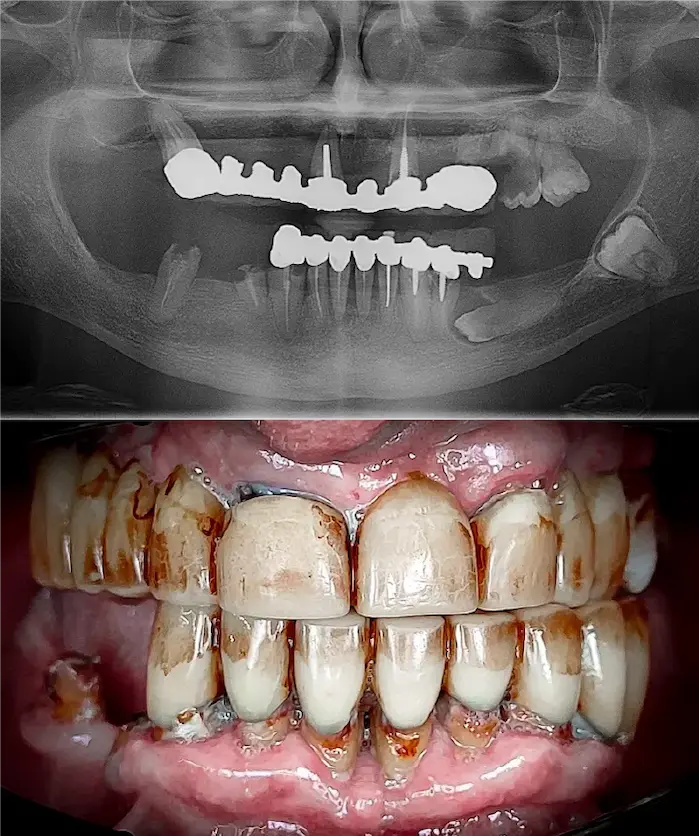

Una soluzione esiste: con gli impianti dentali zigomatici e gli impianti subperiostali (o impianti sottoperiostei) puoi ottenere denti fissi anche in assenza totale di osso mascellare.

Gli impianti dentali zigomatici fissi sono impianti in titanio lunghi 3 – 6 cm che si ancorano all’osso zigomatico, molto più denso e stabile dell’osso mascellare. In base alle necessità il chirurgo definirà se utilizzare un impianto Zygoma Quad (due impianti zigomatici per lato), Zygoma Hybrid oppure Zygoma Laterale.

Gli impianti sottoperiostei (o impianti subperiostali) vengono creati su misura, in titanio puro T4 completamente biocompatibile, e applicati sulla superficie dell’osso residuo.

Sono progettati digitalmente per adattarsi alla tua anatomia in presenza di atrofia ossea severa.